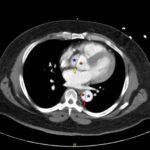

Acute aortic dissection is a life-threatening event caused by separation of the aortic layers that requires prompt management and surgical consultation. We present the case of a 53-year-old male who developed acute, severe chest pain radiating to his back at a community hospital and was transferred to a tertiary center for definitive surgical management. The patient’s aortic dissection was diagnosed via computed tomography angiography. He was started on rate-control and blood pressure medications, and was admitted emergently to the operating room. Emergency physicians should obtain immediate surgical consultation, promptly start medications for rate and blood pressure control, and administer analgesia in order to stabilize their patient and decrease the shear forces that would further propagate an aortic dissection.